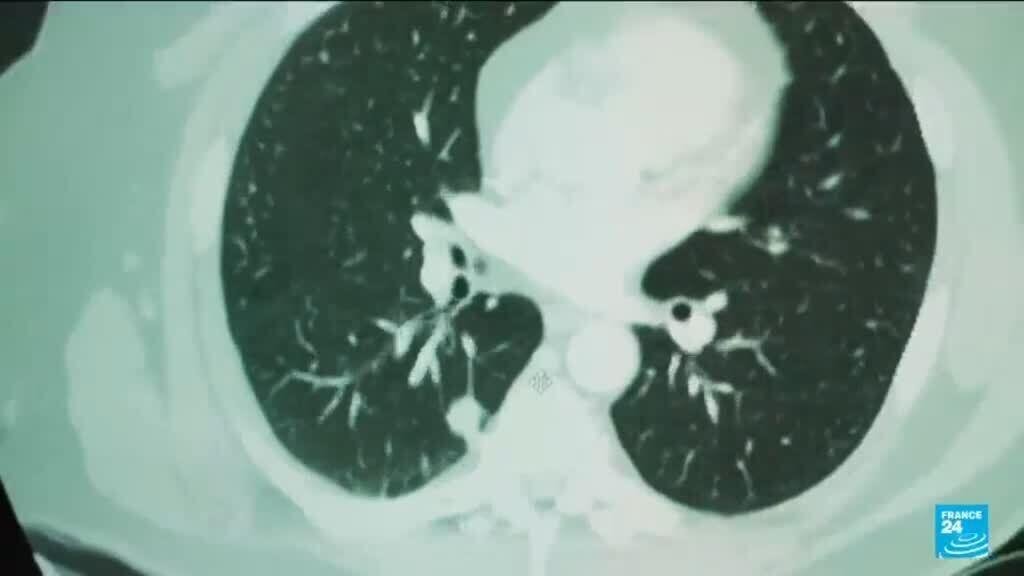

Artificial intelligence is making significant strides in healthcare, particularly in the realm of breast cancer diagnostics. By harnessing advanced algorithms, AI systems can analyze mammograms with remarkable precision, highlighting areas of concern that might be overlooked by the human eye. This capability not only improves detection rates but also allows for earlier interventions, which can be crucial for effective treatment.